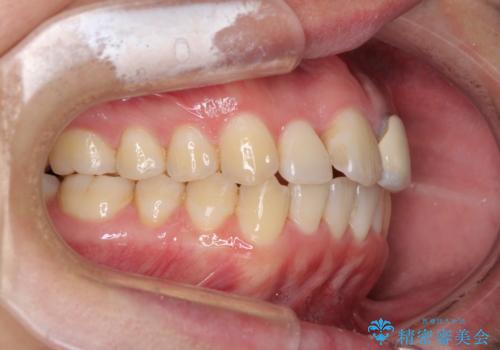

前歯の歯並びとクラウンを改善 インビザラインとオールセラミック

- 前歯の歯並びと不自然な色をした前歯のクラウンを気にして来院された患者様です。

上下前歯の歯列不正はインビザラインにより歯列を整え、その後に、前歯をオーダーメイドタイプのオールセラミッククラウンにて補綴治療することとしました。

初診時には、歯並びを整えることのみを検討されていましたが、歯列が整うにつれて不自然な色合いが気になるようになり、矯正治療を行ってから補綴治療をする計画を受け入れてくださいました。